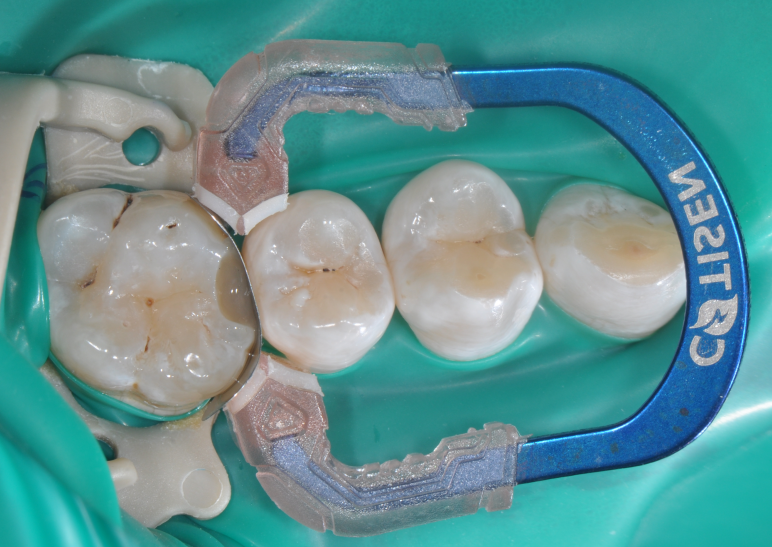

牙医-马小寒【实操病例】

右上6号牙位的近中,可见隐约龋坏